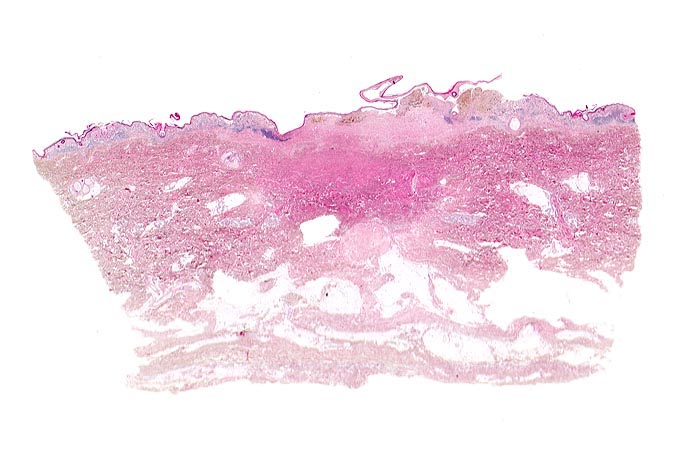

PathoPic ID 3474 - Malignes Melanom

Malignes Melanom

maligner Tumor

Haut, untere Extremität

Haut

Asymmetrische, in der oberen Dermis gelegene pigmentierte Läsion (braun) mit begleitendem perifokalem Entzündungsinfiltrat (blau).

Stellenweise erhabene, unregelmässig begrenzte und inhomogen gefärbte braun-schwarze Hautläsion.

Rasch gewachsene Hautläsion am Unterschenkel.

Histologie

Scan